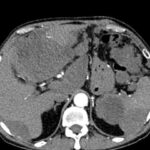

Epigastric port recurrence invading falciform ligament and adjacent liver

Recurrent nodule in GB fossa invading transverse colon

CT showing recurrent disease 2016